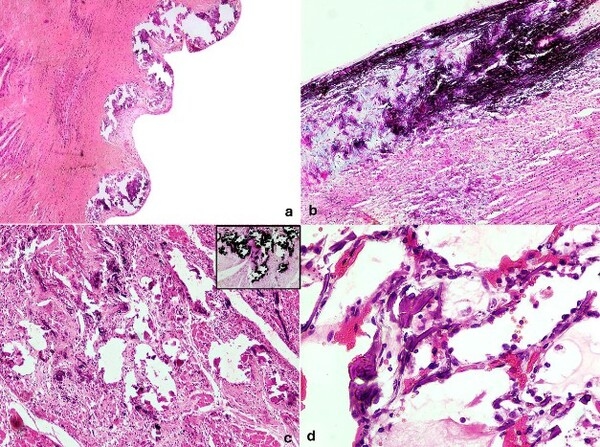

[Figura 2: Hallazgos microscópicos. A y B) Mineralización severa de la capa íntima y media de la aorta. C) Mineralización de miofibrillas en el corazón. D) Mineralización intra-alveolar en pulmón.]

Patología: La huella indeleble de la mineralización Las necropsias confirmaron que el daño tisular es severo e irreversible. En los 30 animales necropsiados se observó mineralización sistémica de los grandes vasos. La aorta y las arterias carótidas son las más afectadas, perdiendo su elasticidad y presentando placas blanquecinas, rugosas y elevadas, que a menudo coalescen.

A nivel microscópico, se describió una mineralización difusa severa de las capas íntima y media de la aorta, y frecuentemente metaplasia osteocondroide. El corazón también se vio comprometido en gran parte de los casos, con mineralización de las válvulas y el endocardio. Estas lesiones explican la insuficiencia cardiovascular y la pobre condición corporal que no responde a tratamientos nutricionales o antiparasitarios.